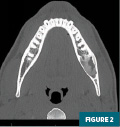

Noncontrast CT imaging of the facial bones and adjacent soft tissues was subsequently performed in November 2024 for presurgical planning with axial, coronal, and sagittal images reconstructed (Figures 1 to 6). CT revealed a partially heterogeneous, predominantly moderately high-attenuation, sharply circumscribed, expansile lesion within the left hemimandible extending to the angle of the mandible and the adjacent mandibular canal. The lesion measured approximately 3.2 cm anteroposterior by 1.6 cm transverse by 1.7 cm craniocaudal and demonstrated contiguity with the roots of the left first and second mandibular molars. The adjacent left third molar was surgically absent. The lesion was noted to show mild, diffuse, concentric cortical thinning. However, no disruption of overlying cortical bone was noted. No abnormalities in the adjacent soft tissues were present.